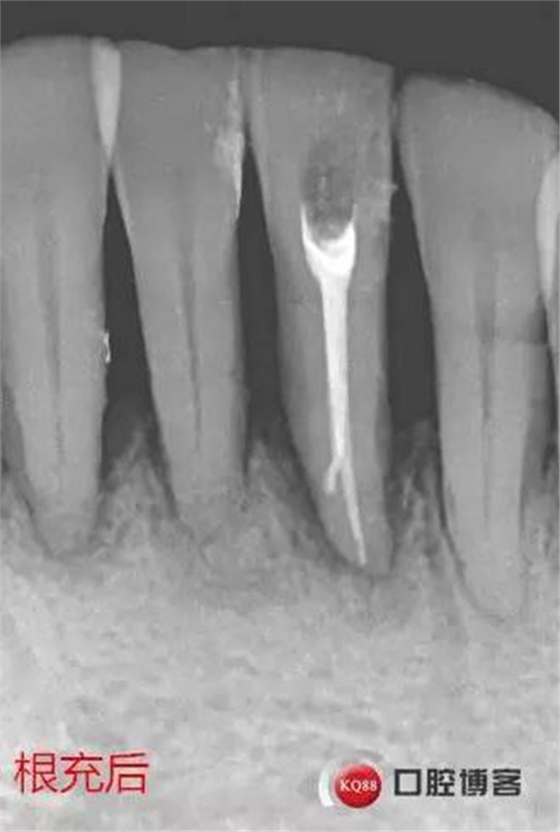

處理:31去暫封,疏通根管,沖洗,試尖,拍片,根充,拍片,恰填,根尖孔外無(wú)多余藥物滲出。樹(shù)脂充填開(kāi)髓孔。33-43樹(shù)脂纖維帶固定,調(diào)合拋光。

5、一切按標(biāo)準(zhǔn)施行,不能再圖省事、偷工減料。